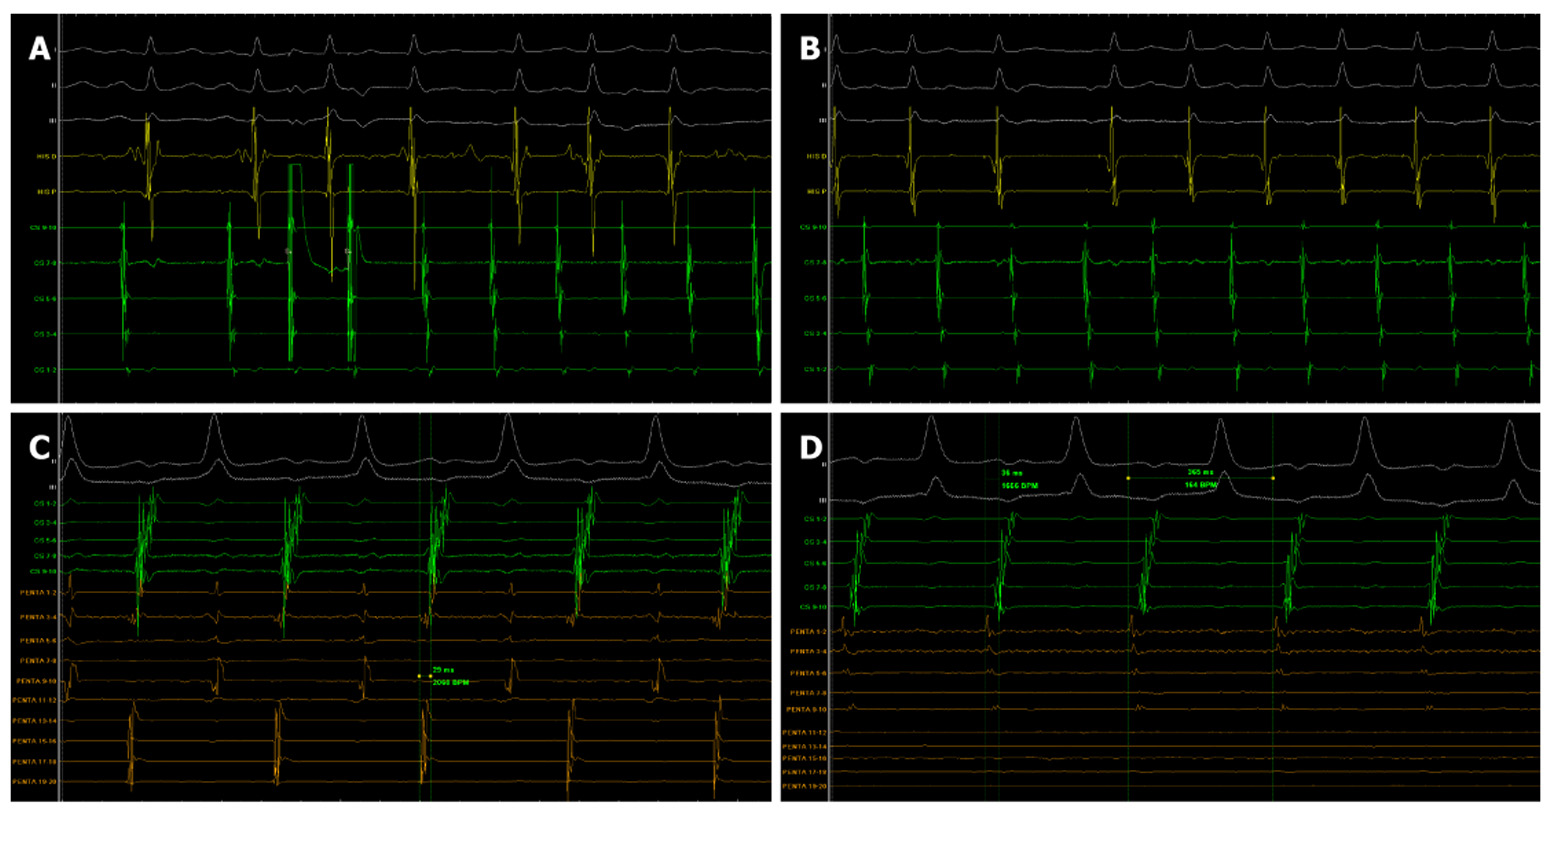

- Silent triggers and symmetric peduncles - a rare presentatio... 2025-10-11